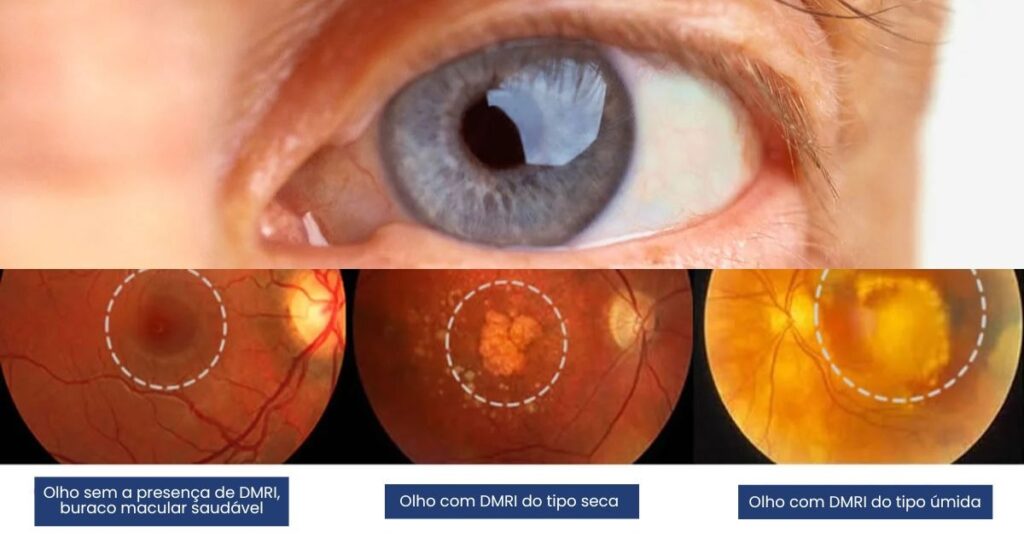

1. DMRI seca (ou atrófica)

É a forma mais comum, representando cerca de 85–90% dos casos. Ocorre quando há um desgaste progressivo das células da mácula (atrofia), resultando em visão borrada e perda gradual da nitidez.

- Relacionada ao acúmulo de drusas (depósitos amarelados sob a retina)

2. DMRI úmida (ou exsudativa)

É a forma menos comum, porém mais agressiva. Caracteriza-se pelo surgimento de vasos sanguíneos anormais sob a retina (neovascularização). Esses vasos são frágeis e costumam vazar sangue e líquido, causando perda rápida da visão central.

Mostra cortes detalhados da mácula, revelando drusas, atrofias ou acúmulo de líquido. É essencial no monitoramento.

5. Retinografia

Documenta imagens fotográficas da mácula para acompanhamento anual.